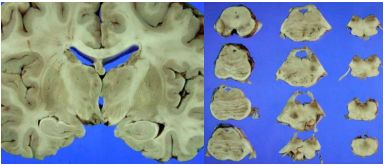

98. 16 歲女孩被父母帶來急診,症狀為這兩週開始漸進性頭暈、目眩、合併病態 不穩,最近一個月經常性原因不明嘔吐,體重減輕兩公斤。病患檢查爲意識清 楚,無發燒,有營養不良與言語不清,複視(diplopia)、旋轉性眼球震顫 (rotatory nystagmus) 、及四肢輕癱 (quadriparesis)。病患非素食主義者也無酗 酒。住院治療期間因心因性休克而過世,病理解剖之腦部如下圖:

以下何者爲最可能的診斷? (A)Mitochondrial Encephalomyopathy (B)Wernicke encephalopathy (C)Multiple sclerosis (D)Cobalamin deficiency related neurological disea